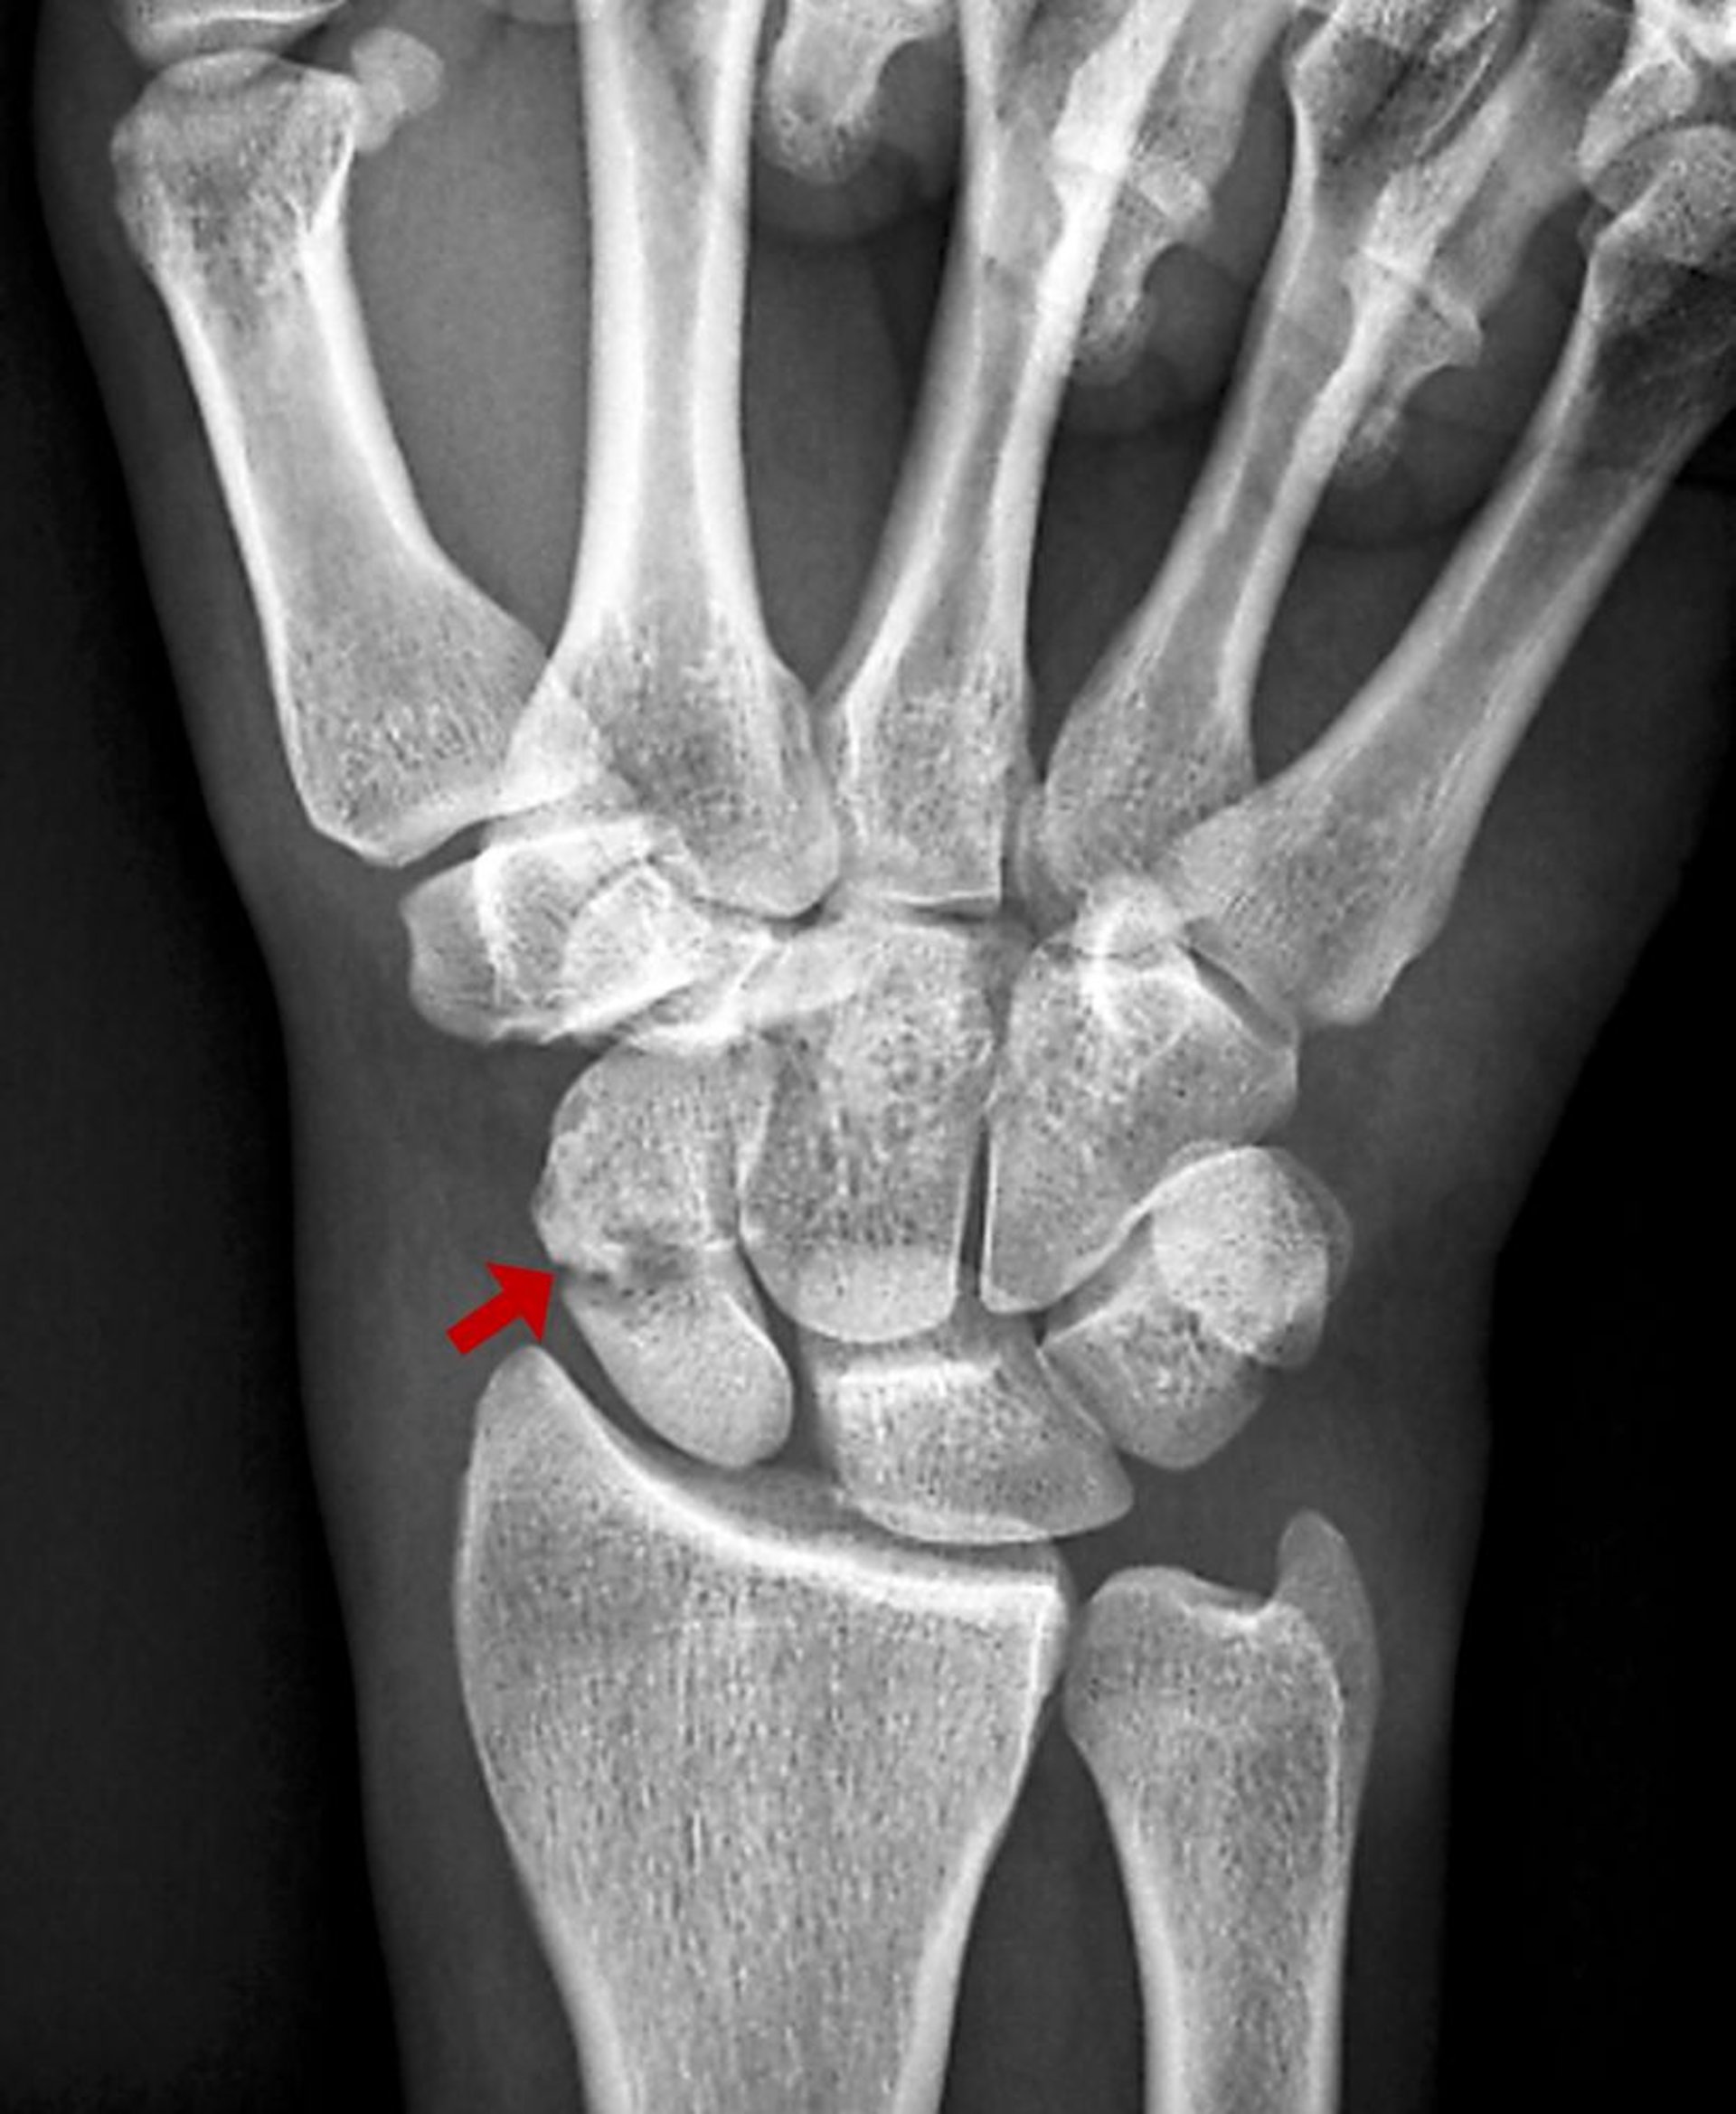

Diese Kahnbeinfraktur ist auf dem Röntgenbild als Bildaufhellung sichtbar.

ZEPHYR/SCIENCE PHOTO LIBRARY